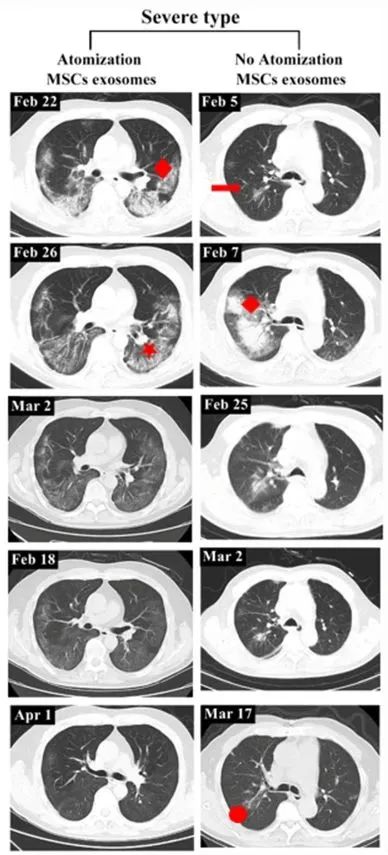

重度患者前后影像變化:以患者 2 為例,該患者從 2020 年 2 月 27 日開始接受外泌體治療,3 月 18 日,患者的 CT 掃描顯示雙肺病變明顯吸收,病變密度消退。4 月 1 日,該患者肺部病灶完全吸收。而未接受外泌體治療的重度患者,吸收肺病灶后仍然存在纖維臍帶陰影。

左:患者 2;右:無外泌體霧化治療的重度病例